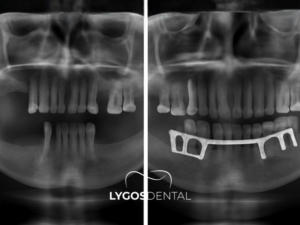

Subperiostal implant, çene kemiği yüksekliği yetersiz olduğunda ve kemik içine implant yerleştirilemediğinde tercih edilir. Bu yöntem genellikle ileri derecede kemik kaybı bulunan hastalarda uygulanır. Çene kemiğinin implant için yeterli hacme sahip olmadığı durumlarda tercih edilebilir.

Kemik grefti gibi ek cerrahi işlemler uygun olmadığında alternatif oluşturur. Uzun süre dişsiz kalan kişilerde kemik erimesi gelişebilir. Bu durum klasik implant uygulamasını zorlaştırabilir. Subperiostal implant, kemik üzerine yerleştirilen özel yapısı sayesinde bu tür vakalarda destek sağlayabilir.

Subperiostal İmplant ile klasik implant arasındaki en temel fark, implantın kemiğe yerleşim biçimidir. Klasik implant sistemlerinde implant, çene kemiğinin içine yerleştirilir ve zaman içinde kemikle bütünleşmesi beklenir. Subperiostal İmplant sisteminde ise taşıyıcı yapı kemiğin içine değil, kemiğin üzerine konumlandırılır ve diş eti altından destek alınır.

Subperiostal İmplant planlanmadan önce son derece ayrıntılı bir değerlendirme yapılması gerekir. Bu aşamada çene kemiğinin mevcut hacmi, yüzey formu, diş eti kalınlığı, ağız içi destek dokular ve kapanış ilişkisi dikkatle incelenir. Ayrıca protezin nasıl taşınacağı, yüklerin nasıl dağıtılacağı ve sistemin uzun vadede nasıl korunacağı da planlama sürecinin önemli parçalarıdır. Çünkü Subperiostal İmplant sıradan bir implant uygulaması gibi düşünülmemelidir.